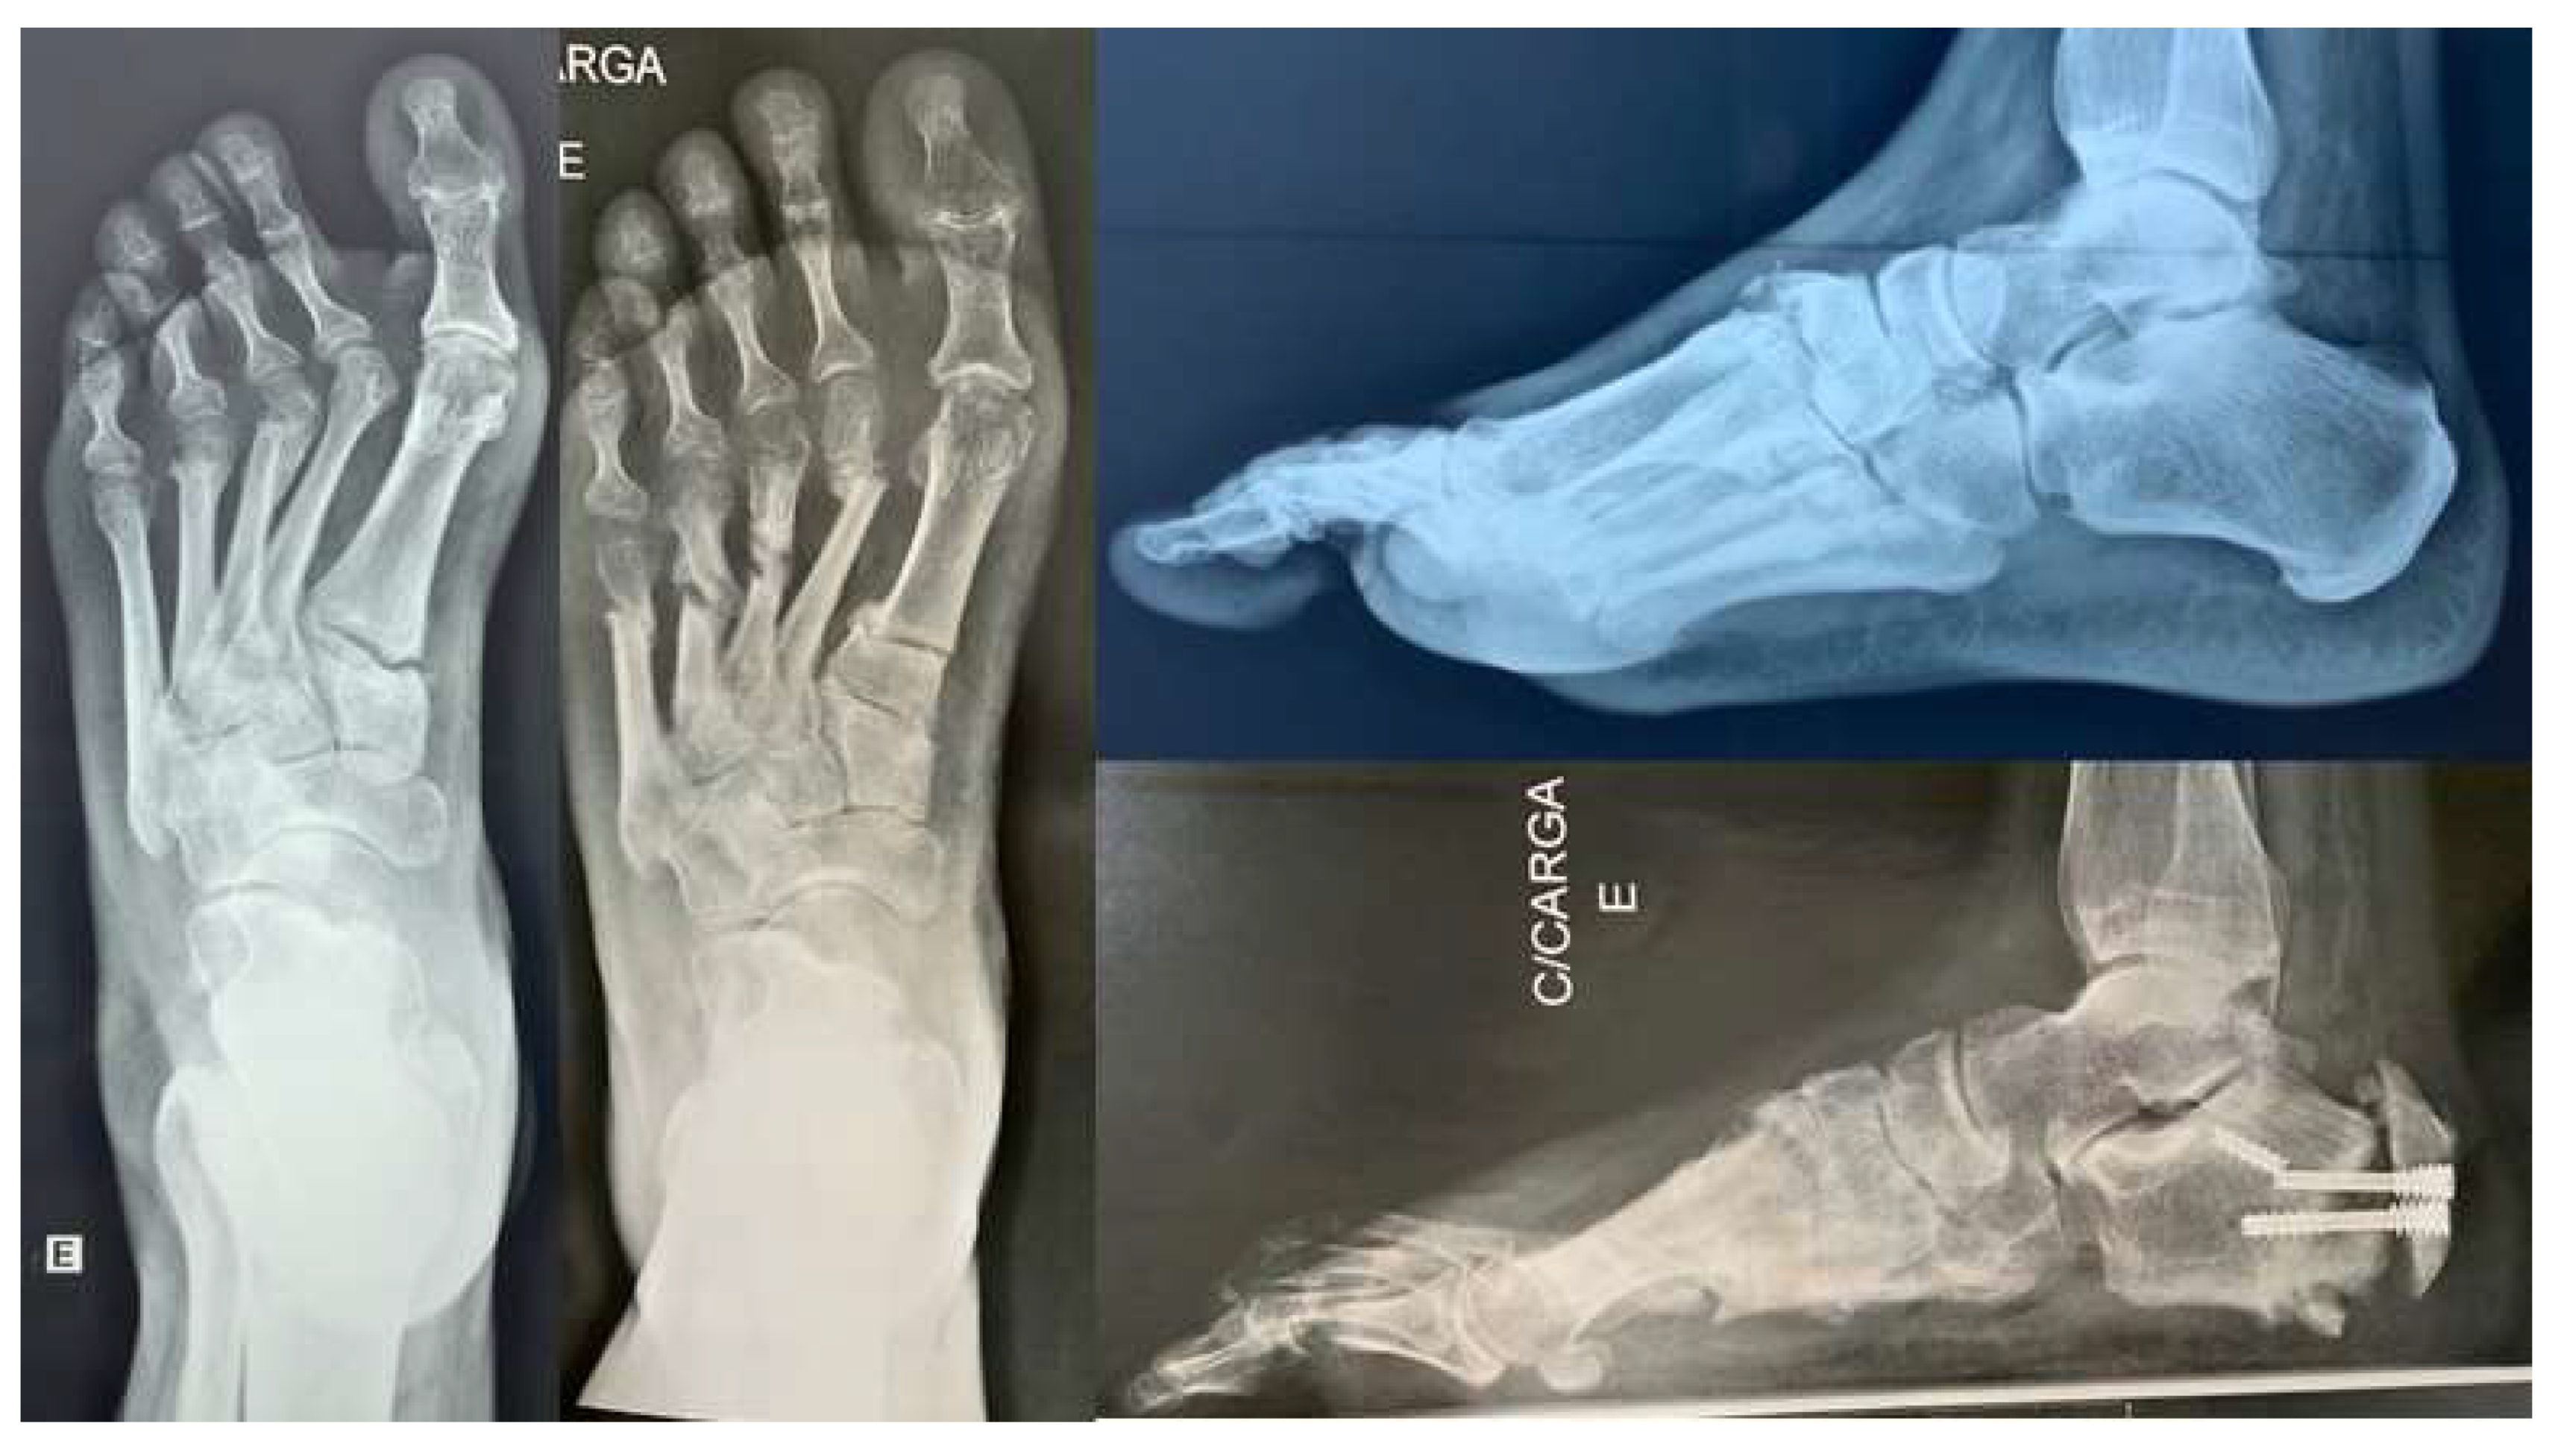

One patient with a Charcot sequela deformity evolved to delayed consolidation with screw fracture (Figure 4). Three cases (15%) evolved to incomplete correction, but only one (33.33%) required additional surgery. These incomplete correction cases belonged to the initial cases. No wound complications or non-consolidation of the cuboid bone or first metatarsal osteotomies were observed. (Figure 5).

Figure 4. Delayed calcaneal consolidation in a Charcot sequela deformity.

Figure 5. (A) We had full consolidation of cuboid and first metatarsal bones without fixation and with immediate weight bearing. (B) Clinical improvement of hindfoot alingment.